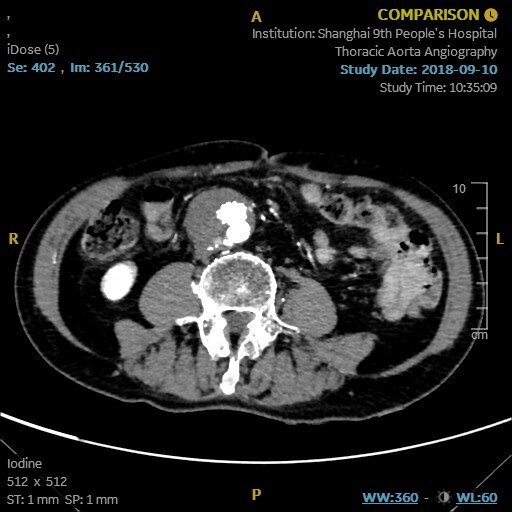

腹主動脈瘤破裂腹主動脈瘤(AAA)是身體最大的動脈——主動脈在腹部部分的擴張。隨著時間的推移,動脈瘤生長緩慢,小動脈瘤通常沒有任何癥狀。然而,較大的動脈瘤和迅速擴大的動脈瘤會引起癥狀,甚至破裂或夾層。AAA破裂和夾層是危及生命的情況,可引起嚴重的低血壓、頭暈、心率加快和突然的劇烈腹痛,如果不能識別和適當治療,將導致嚴重的發(fā)病率和死亡率,未經治療的死亡率接近100%。中間綠色部分為腹主動脈雖然許多AAA患者(腹主動脈直徑大于3cm)被確定為接受了搶先修復術,從而降低了死亡率,但多達50%的主動脈瘤患者的主要表現(xiàn)是動脈瘤破裂。破裂主動脈瘤患者的死亡率難以計算,但據(jù)國內外文獻報道,歷史上的急性死亡率高達90%,而采用當前外科手術方式的急性死亡率高達75%。AAA好發(fā)于65~85歲男性。這些動脈瘤在破裂前通常無癥狀,破裂是一種災難性的并發(fā)癥。導致動脈瘤擴張的原因有直接創(chuàng)傷、慢性感染、急性感染、炎癥等。動脈粥樣硬化性主動脈壁損傷被認為是AAA發(fā)生的主要危險因素,這種傳統(tǒng)觀點最近受到了挑戰(zhàn)。67歲男性,已知腹主動脈瘤,有腰背部和右側腹股溝疼痛3個月的病史。患者行腰椎及骨盆MRI檢查。MRI后立即獲得的連續(xù)軸位CT血管成像(CTA)顯示右側腹膜后大量血腫,并伴有造影劑從主動脈后外側外滲(箭頭)。手術中,看到右側腹膜后大量血腫,病理評估顯示主動脈壁不連續(xù)區(qū)域和相關的機化性血腫。當主動脈壁的機械應力超過壁組織的抗拉強度時,AAA破裂。雖然最初認為簡化的拉普拉斯定律(LawofLaplace)可以預測壁面應力,但實驗證據(jù)表明,壁應力的預測更加復雜,因為它受到動脈瘤位置、結構和腔內血栓的影響。TIPS:拉普拉斯定律是物理學和數(shù)學中的基本原理,它描述了充滿液體的容器內的壓力和容器壁的張力之間的關系。當考慮到動脈中形成的壓力時,它特別相關。簡單地說,拉普拉斯定律就是血管內的壓力與管壁的張力成正比,與血管的半徑成反比。在數(shù)學上,可以表示為:P=2T/r;其中P為壓力,T為張力,r為容器半徑。不同角度的VonMises壁應力輪廓圖,在收縮壓峰值時患者特定的腹主動脈瘤幾何形狀。中間的圖是截面圖。動脈瘤后壁存在高應力區(qū),而近端瘤頸處為壁應力峰值。腹主動脈瘤的大小和擴張速度是預測破裂的最重要因素AAA的大小和擴張速度是預測破裂的最重要因素。根據(jù)一般共識,較大動脈瘤患者應接受手術治療。較小動脈瘤的臨床治療方法存在爭議。對于4.0~5.5cm小動脈瘤的處理,目前臨床研究較少。結論表明,早期介入治療與動脈瘤直徑≥5.5cm時介入治療患者的生存率相似。米國退伍軍人管理局的一項研究表明,早期干預可降低手術并發(fā)癥。在快速擴張的動脈瘤中可以觀察到與初始大小無關的主動脈壁裂隙和破裂。多項研究也顯示,動脈瘤破裂家族史可使腹動脈瘤破裂的風險增加數(shù)倍。另外,與無破裂家族史的患者相比,有破裂家族史的患者發(fā)生動脈瘤破裂的年齡較早(65歲vs.75歲)。大多數(shù)AAA患者的動脈瘤直徑小于5.5cm。由于5.5~5.9cm動脈瘤的1年破裂發(fā)生率顯著增加至9.4%,因此這是手術修復風險低于破裂風險的通常閾值。此外,增加超過0.5cm的動脈瘤破裂風險增加,應及時修復。根據(jù)英國和米國的流行病學資料,大約4%~5%的猝死病例繼發(fā)于AAA破裂。只有約50%的AAA破裂患者到達醫(yī)院,破裂情況下的手術死亡率約為50%;然而,很難知道準確的數(shù)字。動脈瘤的易感因素已確定若干易感因素可增加動脈瘤形成的可能性。這些因素包括年齡較大、男性、收縮期和舒張期高血壓、當前或既往吸煙史以及一級親屬有AAA病史。男性50歲后和女性60歲后,接下來的每一個十年,動脈瘤的風險增加。男性患動脈瘤的可能性是女性的4倍,有一級親屬患AAA的風險增加4倍。吸煙是最重要的可糾正的危險因素,既影響患動脈瘤的可能性,也影響生長加速的速度。病史與體檢雖然理想情況下,患者應該在出現(xiàn)動脈瘤破裂等并發(fā)癥之前就被識別和治療,但超過一半的AAA破裂患者之前有未診斷的動脈瘤,多達30%的AAA破裂患者最初被誤診。據(jù)報道,25%~50%的AAA破裂患者表現(xiàn)為低血壓、腰背痛和搏動性腫塊的典型三聯(lián)征。破裂的可能表現(xiàn)包括原因不明的低血壓、腹股溝疼痛,有時下肢疼痛。其他可能的并發(fā)癥是血尿或消化道出血。因此,對于表現(xiàn)多樣的該病,醫(yī)師應高度懷疑該疾病,并降低評估閾值。在臨床表現(xiàn)上,休克程度因部位、大小和延遲表現(xiàn)而異。前外側壁的破裂直接與腹腔相連,所以通常導致當場死亡有關。后外側壁破裂與腹膜后間隙相通,因此病人通常存活。小破裂較大破裂失血量少,小破裂可初步封閉破裂于腹膜后,減少失血量。據(jù)報道,體格檢查發(fā)現(xiàn)搏動性腫塊的敏感性為51%~100%。研究表明,動脈瘤檢出的總靈敏度隨著動脈瘤大小的增加而增加,對3.0~3.9cm動脈瘤的靈敏度為29%,對4.0~4.9cm動脈瘤的靈敏度為50%,對>5.0cm動脈瘤的靈敏度為76%。肥胖已被證明會降低檢測的準確性。Grey-Turner征,即血液沿腹膜后剝離而累及脅部的瘀斑罕見,但在某些病例中可檢測到外側壁的堅實性。診斷與治療對于血流動力學不穩(wěn)定的患者,可僅根據(jù)癥狀(低血壓、腰背痛和腹部搏動性包塊)或通過床旁超聲確診后將患者送入手術室。對文獻的系統(tǒng)綜述顯示,超聲診斷的靈敏度為98%~100%,特異度為94%~100%。這些結果與在放射科病房進行的超聲篩查相似,后者報告的靈敏度為94%~100%,特異度為98%~100%。腹主動脈瘤(直徑7cm),超聲影像顯示動脈瘤真腔(左下方)與附壁血栓(右上方)主動脈夾層的超聲檢查。在血流動力學穩(wěn)定的患者中,鑒別AAA破裂的首選診斷研究是CT動脈成像(CTA),因為它提供了識別鄰近/受累腎動脈以及動脈瘤形態(tài)的能力。計算機斷層掃描血管造影(CTA)掃描的容積再現(xiàn),一些患者有疊加的動脈瘤節(jié)段。(a,b)患者在t1(左)和t2(右)出現(xiàn)不良演變的圖像。(c,d)患者在t1(左)和t2(右)時的圖像。對于到急診科就診的疑似AAA破裂患者,評估和處置的及時性至關重要,在疑似AAA破裂的病例中,早期與血管外科醫(yī)生會診,同時進行診斷性檢查,有助于促進最終處置到手術室。研究提示,術前液體復蘇策略(包括收縮壓為80~100mmHg的允許性低血壓)可能改善結局。然而,文獻中并沒有隨機對照試驗來證實這些發(fā)現(xiàn)。AAA破裂患者經常需要血液復蘇,往往需要大量輸血。研究表明,自體輸血的患者和較高濃度新鮮冷凍血漿[FFP]輸注的患者(壓積紅細胞[PRBC]:FFP=1:1)有改善的結局。如果不及時治療,AAA破裂在數(shù)小時至一周內幾乎都是致命的。實施開放修復術和血管內修復術的決策復雜,必須考慮患者因素,如年齡、患者合并癥和患者血流動力學狀態(tài)。動脈瘤因素,如位置、大小和形狀;外科醫(yī)生的經驗;以及可用的資源。雖然非隨機研究已經證明血管內修復術可改善發(fā)病率和死亡率,但當這些研究針對患者的血流動力學狀態(tài)進行控制時,這些益處尚未得到證實。此外,對于開放手術PK(比較)?血管內修復術的隨機對照試驗進行的薈萃分析表明,一種修復方法并不優(yōu)于另一種方法。腹主動脈瘤開放修復術腹主動脈瘤腔內修復術腹主動脈瘤腔內修復術前后的CTA影像

李先生,今年67歲,上個月體檢發(fā)現(xiàn)腹部存在搏動性腫塊,很是擔心,立即來到醫(yī)院就診。?6年前因腹主動脈瘤行過微創(chuàng)治療(支架植入),術后恢復良好,1年內CT檢查瘤腔內血栓化。李先生覺得沒啥問題,在隨后的5年中沒有進行過任何隨訪。直至上個月體檢發(fā)現(xiàn)肚子里有搏動性腫塊才趕到醫(yī)院就行治療。內漏是EVAR術后的內漏是導致動脈瘤瘤體繼續(xù)增大甚至破裂,以及需要再次住院和干預治療的最主要原因。約有?20%~50%?的腹主動脈瘤(AAA)患者行腔內修復術(EVAR)后出現(xiàn)內漏,部分內漏可影響患者的近期預后和遠期預后。內漏分為:(1)I型內漏:移植物近遠端錨定部位封閉不良所致;(2)Ⅱ型內漏:側支動脈逆流所致;(3)Ⅲ型內漏:支架結構破損所致;(4)Ⅳ型內漏:由支架覆膜材料縫隙引起;(5)內張力:其中Ⅱ型內漏最為常見,約占全部內漏類型的8%~44%。Ⅱ型內漏是由于與動脈瘤腔相通的側支動脈反流到動脈瘤腔內導致瘤腔不能完全血栓形成,因此瘤腔內壓力持續(xù)存在甚至升高??赡芤稷蛐蛢嚷┑闹饕獋戎в心c系膜下動脈(inferiormesenteryartery,IMA)和腰動脈,也可來源于髂內動脈、副腎動脈或骶正中動脈。隨著EVAR手術的廣泛開展,對Ⅱ型內漏的認知亦逐漸深入和全面,但其轉歸、診治策略以及如何預防等方面依然存在諸多焦點問題。內漏均可阻礙?EVAR?術后瘤體直徑的降低;隨著隨訪時間的延長,內漏可顯著降低?EVAR?術后瘤體直徑的降低幅度,但?II?型內漏與其他類型內漏對于瘤體直徑的影響并無差異。與術后早期發(fā)現(xiàn)的?II?型內漏相比,遲發(fā)性?II?型內漏的瘤體直徑顯著增加。超過?20%?的內漏發(fā)生于?EVAR?術后?2?年以上,16%?的?II?型內漏發(fā)生于術后?1?年以上李先生的腫塊本該在術后變小,但1年后內漏出現(xiàn),導致腫塊沒有明顯縮小,所以體檢再次發(fā)現(xiàn)腹部腫塊。治療方法主要包括腔內手術方法(如經動脈途徑、經腰途徑、經腔靜脈途徑等)和開放手術方法(如開放手術、腹腔鏡等)。?本次通過增強CT發(fā)現(xiàn),內漏為II內漏,來源于右側第四腰動脈,與有髂內動脈相溝通。本次策略采用栓塞的方式,通過微導管進入瘤腔內進行栓塞,注射凝血酶來快速血栓化。